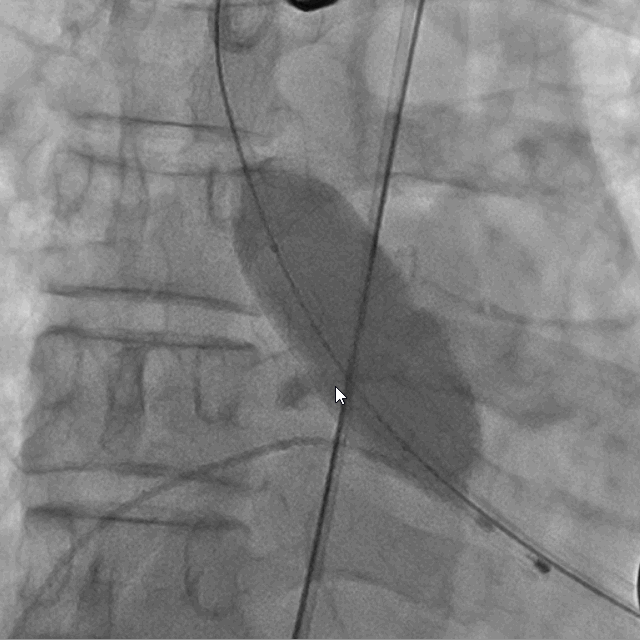

术前DSA造影

术后DSA影像图